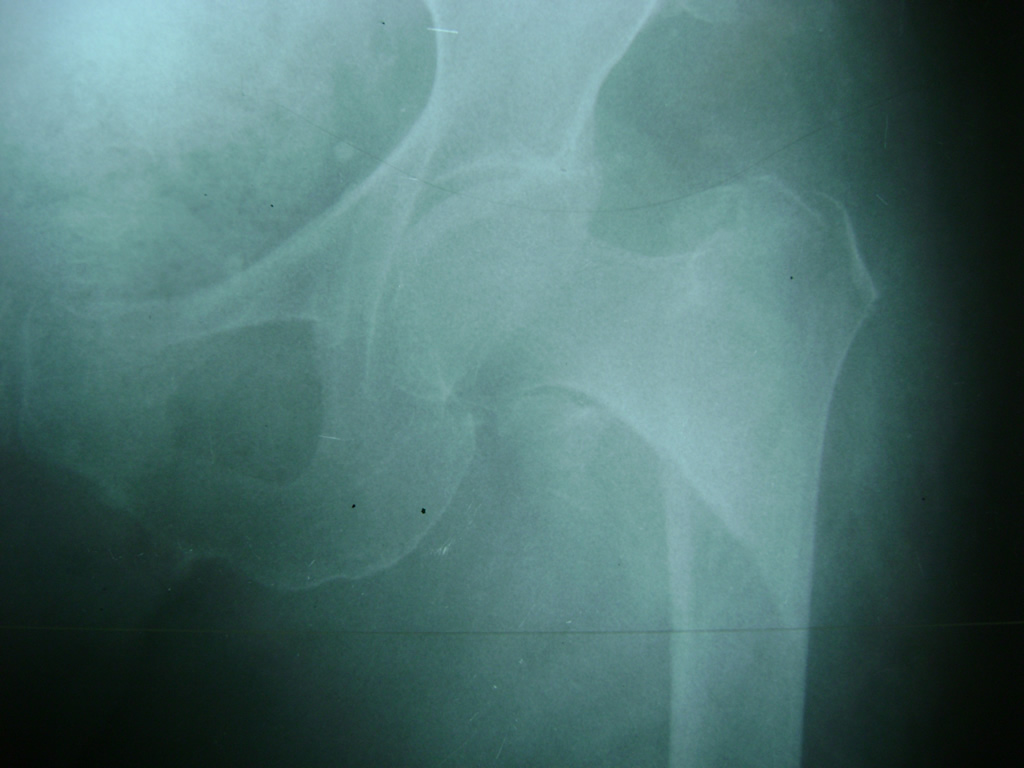

La cirugía de fractura de cadera se realiza para reparar una ruptura en la parte superior del hueso del muslo. Este hueso se denomina fémur.

Es parte de la articulación coxofemoral. Si una fractura de cadera no recibe tratamiento, es posible que deba permanecer en una silla o en la cama.

A menudo se recomienda la cirugía para reparar la fractura debido a dichos riesgos.